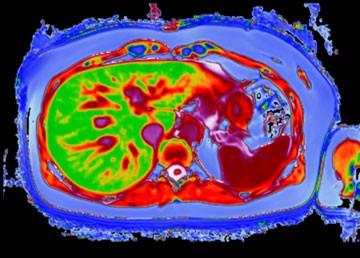

LiverMultiScan is an FDA-cleared, non-invasive, quantitative imaging service, which can aid doctors in the diagnosis of liver disease with a safe, painless MRI scan. LiverMultiScan offers a high-quality method — using ground-breaking technology and rich visual images standardized across sites and manufacturers — to provide the clinician with measures related to the amount of fat, iron and fibro-inflammation in the liver. LiverMultiScan is delivered as a service after an activation protocol is enabled and does not require the purchase of any additional hardware or software.

By integrating Ambra Cloud PACS solution, physicians with LiverMultiScan enabled at their center can get access to images around the clock. Ambra Cloud PACS consolidates multiple imaging systems with one flexible, customizable, and low maintenance cloud storage platform that lets medical imaging be accessed securely anytime, anywhere.